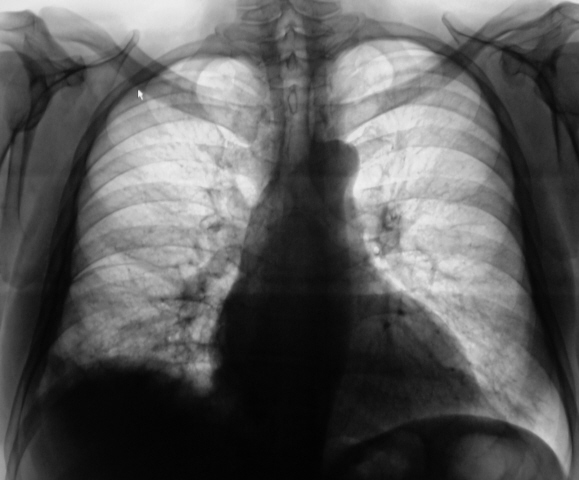

Сегодня произвели "очередной контроль". Произвели рентгенографию в прямой и правой боковой проекциях. Решили также произвести томографию в правой боковой проекции.

Сегодня произвели рентген-контроль. Снимки "выше" - в основном сообщении.

Катенёву В.Л.: На боковых томограммах, впечатление о инфильтрации с распадом в S10; томограммы, вероятно выполнены в положении лёжа, следовательо следует ожидать, что выпот растекся по грудной стенке и  не виден. С учётом характера распада, не исключаеиться туберкулёзный процесс.

О "выпоте" думали даже сначала, но только об осумкованном. Сегодня при дообследовании, "полостное образование" было неожиданной находкой, но о "туберкулёзной" этиологии, именно полостного образования, не думали. Но интересно, что пациент себя (с его слов) чувствует себя хорошо. ПО ВСЕЙ ВИДИМОСТИ, ОТПРАВИМ В ОБЛАСТЬ К ПУЛЬМОНОЛОГАМ.